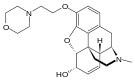

- Esters of morphine opiates: slightly chemically altered but more natural than the semi-synthetics, as most are morphine prodrugs, diacetylmorphine (morphine diacetate; heroin), nicomorphine (morphine dinicotinate), dipropanoylmorphine (morphine dipropionate), desomorphine, acetylpropionylmorphine, dibenzoylmorphine, diacetyldihydromorphine;[261][262]